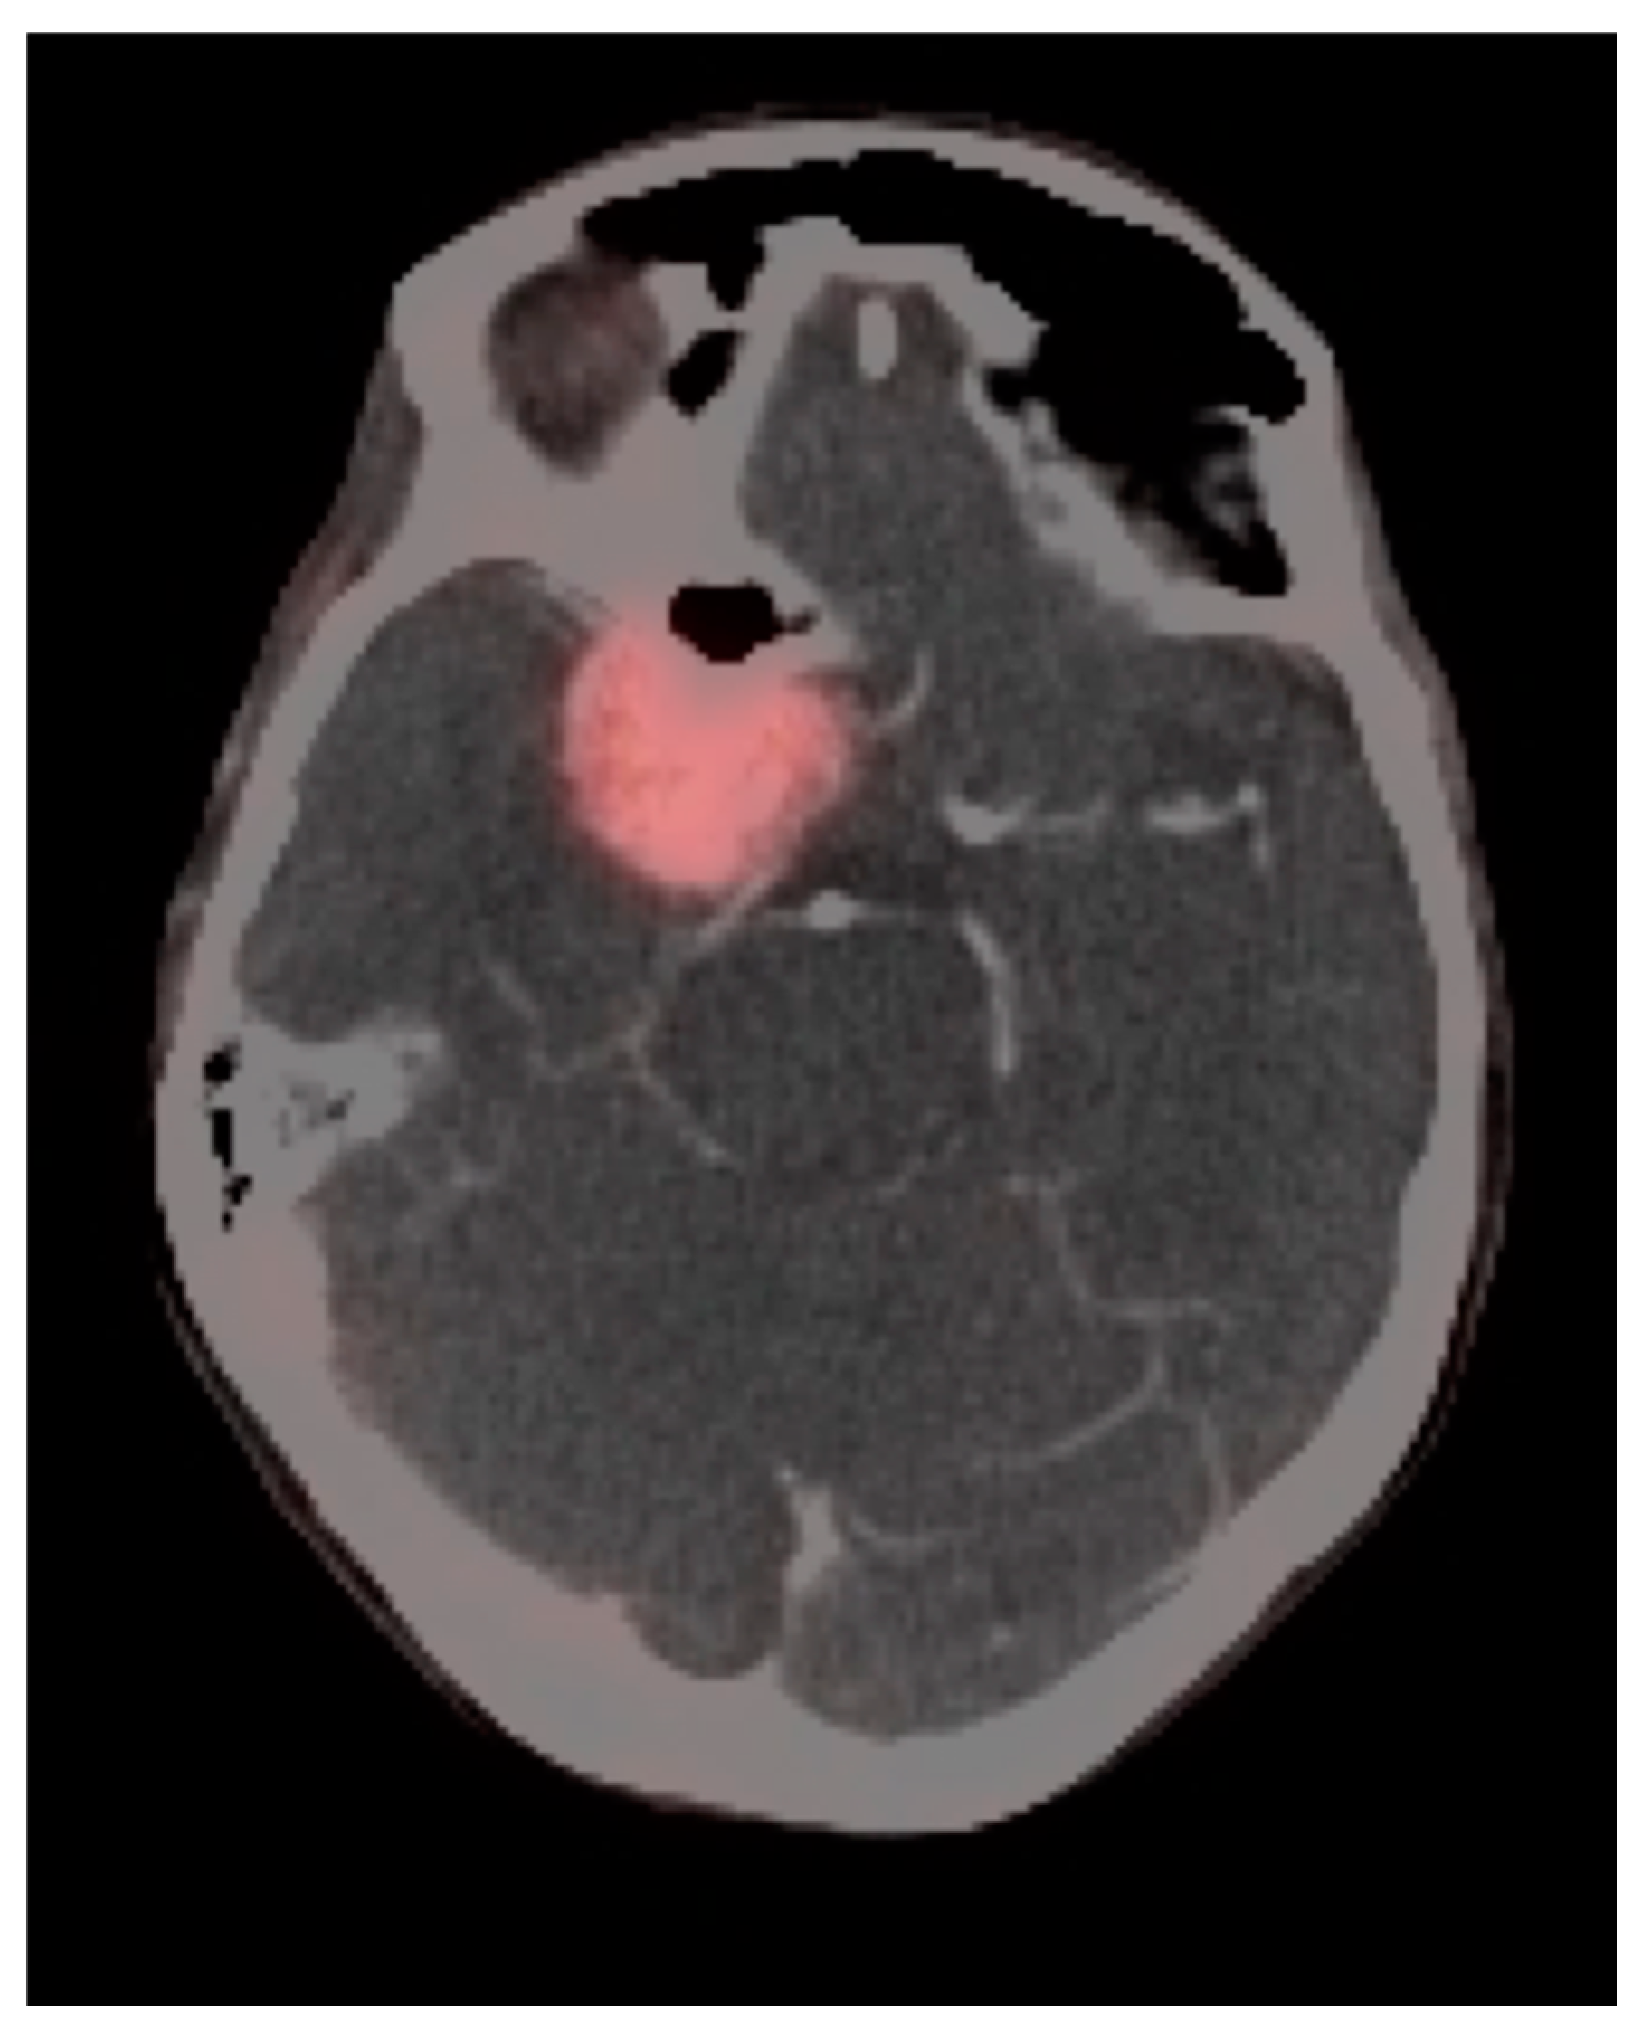

3.3. Primary Brain Tumors

3.4. CNS Lymphoma

3.5. Brain Metastases